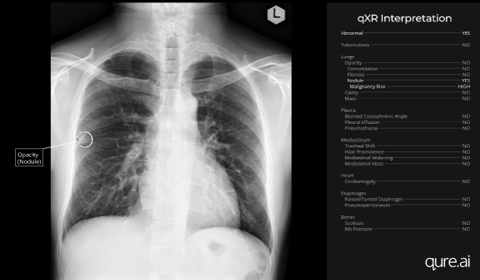

Sept. 11, 2024 — A new study introduced at the International Association for the Study of Lung Cancer (IASLC) 2024 World Conference on Lung Cancer in San Diego, Calif., shows promising initial results using AI-powered chest X-ray interpretation to detect pulmonary nodules which could develop into early-stage lung cancers long before symptoms appear. The retrospective study demonstrated via interim results, an average diagnostic delay of nearly three years from the first abnormal chest X-ray.

The study conducted at the Phrapokklao Hospital’s Cancer Centre of Excellence in Bangkok, Thailand was led by Dr Passakorn Wanchaijiraboon, Medical Oncologist and Deputy Director using the Qure.ai chest X-ray AI solution qXR.

Dr. Passakorn Wanchaijiraboon, while unveiling the poster, said the study "provides a snapshot of the significant potential that AI-assisted chest X-ray analysis holds for transforming early cancer detection and reducing the rate of missed lung cancer diagnoses. In most Thai government hospitals, chest X-rays are interpreted by non-radiologists. However, in community hospitals, there are often no radiologists available to read chest X-rays at all. By overlaying specialist AI to read all cases, we can support clinicians in detecting incidental high-risk nodules that may lead to lung cancer. This approach can streamline decision-making and potentially improve patient survival through the earlier diagnosis of cancer. The implementation of CXR AI is particularly beneficial in the context of community hospitals, where it can significantly enhance diagnostic capabilities in the absence of on-site radiologists.”

The Phrapokklao Cancer Centre study retrospectively reviewed and evaluated the chest X-ray image database of newly diagnosed lung cancer patients over an annual period using qXR. Missed lung cancer was defined as missed in the original report six months prior to a definitive lung cancer diagnosis. 18 percent of patient cases were found to have a missed lung cancer diagnosis over an average period of nearly three years (32.3 months), with a maximum duration of over eight years (96 months) and minimum eight months. Half the patient cases had chest X-rays taken for non-respiratory symptoms as part of a health check-up, categorizing them as "incidentally detected."

This "underscores the transformative potential of AI in the fight against lung cancer,” states Bhargava Reddy, Chief Business Officer, Oncology at Qure.ai. "Overlaying AI on chest X-rays casts the net wider by proactively triaging patients for the risk of lung cancer. It goes beyond people with symptoms or qualifying for screening initiatives based on age or smoking history, to currently invisible and unprofiled patient populations thus detecting lung cancers earlier.”

PHOTO CAPTION: Chest X ray of patient with nodule detected by AI/qXR 23 months prior to the diagnosis of lung cancer. The X-ray was obtained as a part of health check-up.